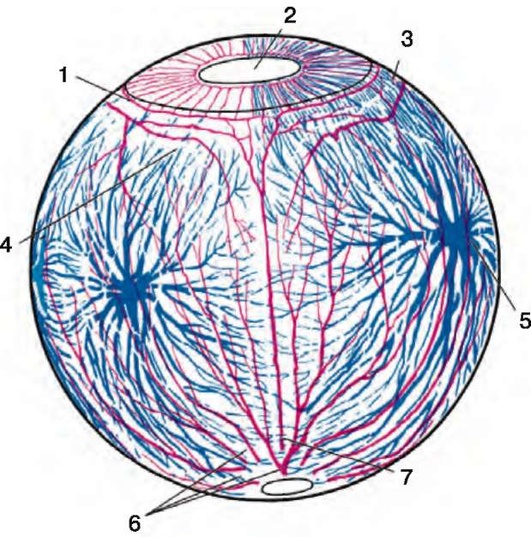

Рис. 4.1. Кровоснабжение глаза: 1 - малый артериальный круг радужки; 2 - шлеммов канал; 3 - большой артериальный круг радужки; 4 - передние конъюнктивальные артерии и вены; 5 - задние конъюнктивальные артерии и вены; 6 - передние цилиарные артерия и вена; 7 - эписклеральные артерия и вена; 8 - сосудистая сеть сосудистой оболочки; 9 - вортикозная вена; 10 - сосудистая сеть сетчатки; 11 - задняя длинная цилиарная артерия; 12 - задняя короткая цилиарная артерия; 13 и 14 - сосуды оболочек зрительного нерва; 15 - цилиарные артерии и вены сетчатки; 16 - сосуды круга Геллера-Цинна

Рис. 4.2. Кровоснабжение глаза: 1 - большой артериальный круг радужки; 2 - зрачок; 3 и 4 - передние цилиарные артерии; 5 - вортикозная вена; 6 - задние короткие цилиарные артерии; 7 - задние длинные цилиарные артерии